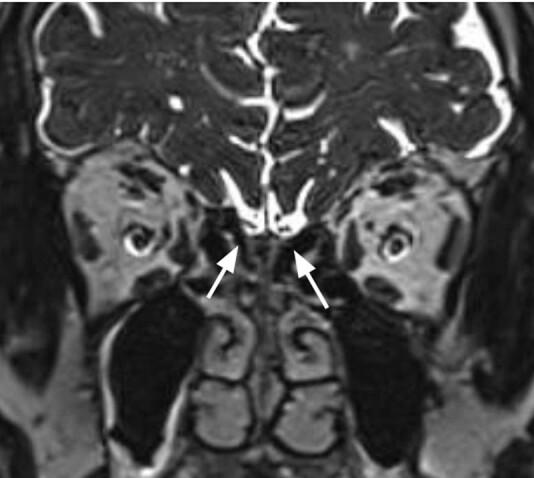

A 76-year-old patient experienced smell disorder, ear fullness and tinnitus 2 days after the first dose of Oxford-AstraZeneca vaccine. The patient then underwent a complete audiological and Ear, Nose and Throat evaluation, nasal endoscopy, Sniffin'Sticks battery, audiometric test battery, and cerebral magnetic resonance imaging (MRI). The exams revealed hyposmia and bilateral reduction of the volume of the olfactory bulbs (OB). At the follow-up, tinnitus was completely resolved while olfactory dysfunction only partially reduced.

A PubMed search was conducted on olfactory and gustatory dysfunctions after COVID-19 vaccination resulting in four case reports with a total of 10 patients. The main symptoms were hyposmia, parosmia, and dysgeusia developed after 1-9 days from vaccination with complete resolution occurring within 1 month. Notably, none of the considered articles reported reduction of OB volumes at cerebral MRI.

病例介绍

一名76岁患者在接种第一剂牛津 - 阿斯利康疫苗后2天出现嗅觉障碍、耳闷和耳鸣。该患者随后接受了全面的听力学及耳鼻喉科评估、鼻内镜检查、嗅觉棒测试、听力测试电池以及脑部磁共振成像(MRI)。检查显示嗅觉减退以及双侧嗅球(OB)体积减小。随访时,耳鸣完全缓解,而嗅觉功能障碍仅部分减轻。

对COVID - 19疫苗接种后的嗅觉和味觉功能障碍进行了PubMed检索,结果有4篇病例报告,共10例患者。主要症状为接种疫苗后1 - 9天出现的嗅觉减退、嗅觉异常和味觉障碍,1个月内完全缓解。值得注意的是,所查阅的文章均未报告脑部MRI显示嗅球体积减小。